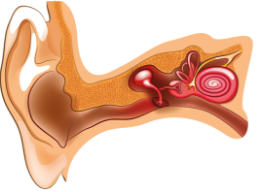

Середній отит

Середній отит - це запальне захворювання середнього вуха, пов'язане з потраплянням в нього інфекції.

Гострий середній отит - одне з найпоширеніших захворювань дитячого віку. До трирічного віку гострий середній отит переносить 71% дітей, а за перші 7 років життя до 80% дітей мають в анамнезі хоча б один епізод цього захворювання.

У більшості випадків запальний процес середнього вуха не є первинним захворюванням. Як правило, він є ускладненням зовнішнього отиту або інфекційних захворювань верхніх дихальних шляхів - тонзиліту, риніту, гаймориту, а також гострих вірусних захворювань - грипу, кору, скарлатини.

Внутрішній отит (Лабіринтит)

Лабіринтит - це запалення внутрішнього вуха. Лабіринтит з усіх різновидів отитів становить найбільшу небезпеку. При запаленні внутрішнього вуха типові симптоми включають порушення слуху, вестибулярні порушення - запаморочення, втрату рівноваги і орієнтації в просторі. Лікування внутрішнього отиту проводиться під наглядом лікаря з урахуванням етіології і патогенезу захворювання.